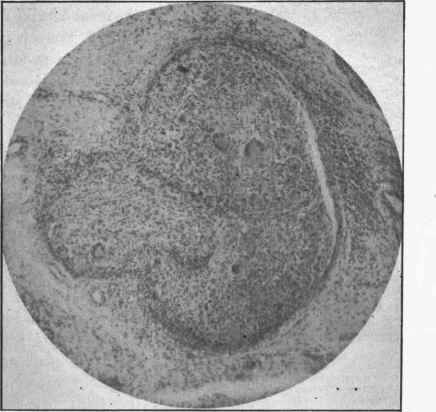

The disease begins usually in the Synovial membrane, and consists in a formation of tubercles and a chronic inflammation with great production of granulation tissue. The soft, pulpy granulation tissue gives the synovial membrane a gelatinous appearance, from which one of the names of the disease is taken. There is also a slow enlargement of the joint from the increased bulk of the synovial membrane. The pulpy gelatinous tissue often presents to the naked eye distinct white bodies, the miliary tubercles, and under the microscope the most typical tubercles are visible, as shown in Fig. 299, and also in Fig. 129, p. 308.

Fig. 299. - A group of tubercles with giant-cells In tuberculosis of the synovial membrane, x 00.